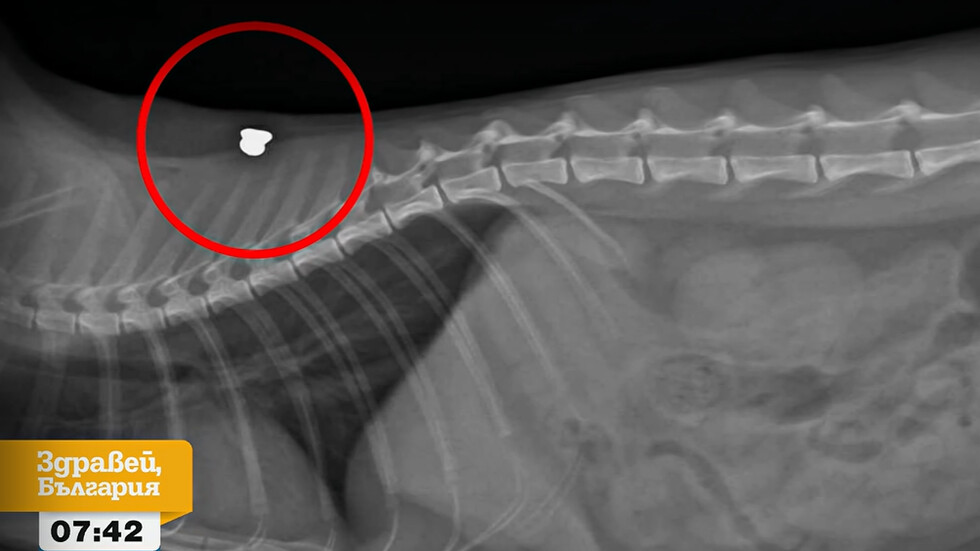

"Още при първия преглед преглеждащият лекар установи, че има входна рана и директно каза, че за нея това е прострелване с въздушна пушка", обяснява друга жителка. Рентгеновите снимки потвърждават съмненията, като ясно показват сачми, заседнали в телата на котките.